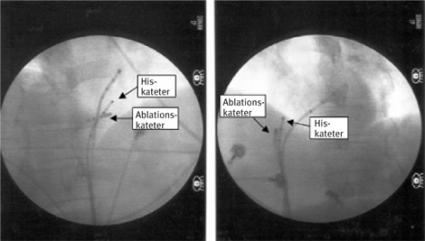

Samtliga patienter med AV-återkopplings- och förmakstakykardier behandlades framgångsrikt med kryoablation, vilken i de flesta fall skedde i omedelbar närhet till den kateter som placerats för att lokalisera His´ bunt. Hos tre patienter utvecklades under testfrysning övergående AV-block, vilket medförde justering av kateterpositionen, och slutgiltig ablation kunde utföras utan bestående påverkan på den AV-nodala överledningen. En patient återfick sin takykardi efter en månad och behandlades med upprepad kryoablation och har sedan dess varit besvärsfri.

Vi har nyligen presenterat våra initiala erfarenheter av posterior modifiering med kryoteknik [23]. Våra resultat med 97 procent primärt lyckade ingrepp är helt i paritet med dem som redovisas för radiofrekvensablation. En bidragande orsak kan vara att vi använt en kryokateter med 6 mm lång spets, till skillnad från tidigare studier där man använt en 4 mm lång kateterspets. En annan anledning kan vara metoden att utföra testfrysning i potentiella ablationslägen tills en optimal position lokaliserats. I flera fall levererades den effektiva ablationsapplikationen mycket nära AV-noden och His´ bunt och i lägen där vi hade tvekat eller avstått från att använda radiofrekvensenergi (Figur 3). Recidivfrekvensen i vårt material överensstämmer med den som rapporterats vid radiofrekvensablation [4-6]. Vi hade inga komplikationer i form av bestående AV-block.